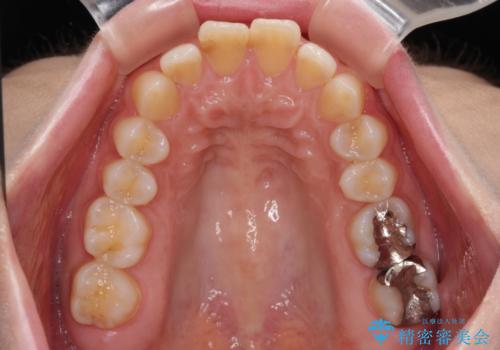

- 上の前歯が出っ歯と突出した口元を気にして来院された患者様です。

上顎歯列全体が前方に飛び出している印象であったので、上顎左右の第一小臼歯2本を抜歯し、ワイヤー装置にて抜歯矯正を行うこととしました。